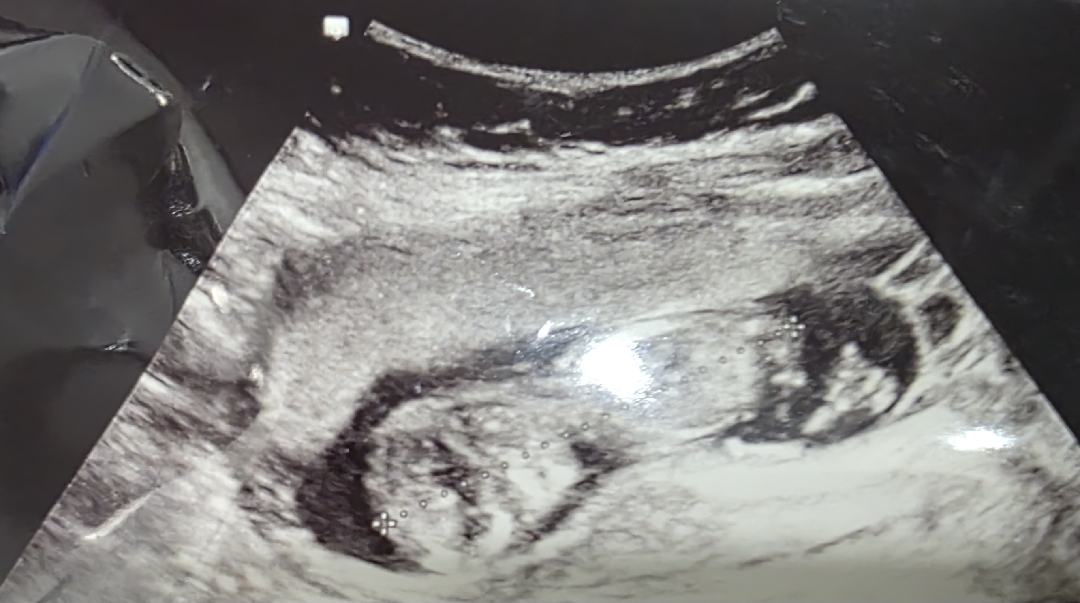

각도법 봐주세요~

아들 일까요?딸 일까요? 봐도 모르겠어요 ㅠㅠㅠㅠ